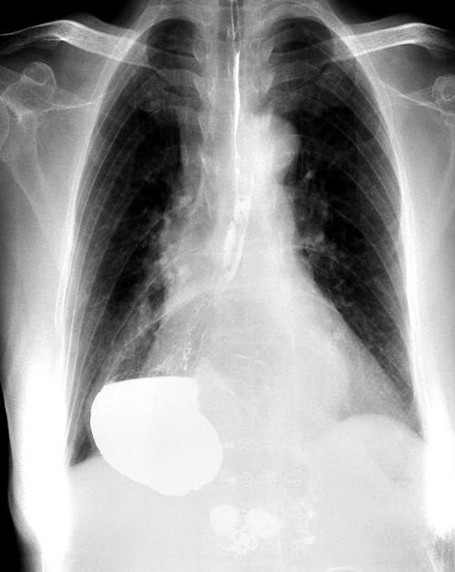

術(shù)前胃“游走”到胸腔。重慶市人民醫(yī)院供圖

接診的胸外科副主任醫(yī)師馬洪飚經(jīng)過詳細詢問及完善相關(guān)檢查,發(fā)現(xiàn)王婆婆所患的疾病叫“食管裂孔疝”,由此造成了胃的“離家出走”,有一部分跑到了胸腔里面,才會出現(xiàn)上述不適。

在完善術(shù)前準備后,胸外科主任馬錚帶領馬洪飚副主任醫(yī)師、張兵兵主治醫(yī)師通過微創(chuàng)手術(shù)不僅將王婆婆游走到胸腔的胃還納到了腹腔,還修補了拳頭大小的食管裂孔,以防止胃再次離家出走。手術(shù)后王婆婆恢復順利,術(shù)前的不適癥狀消失,目前已經(jīng)順利出院。